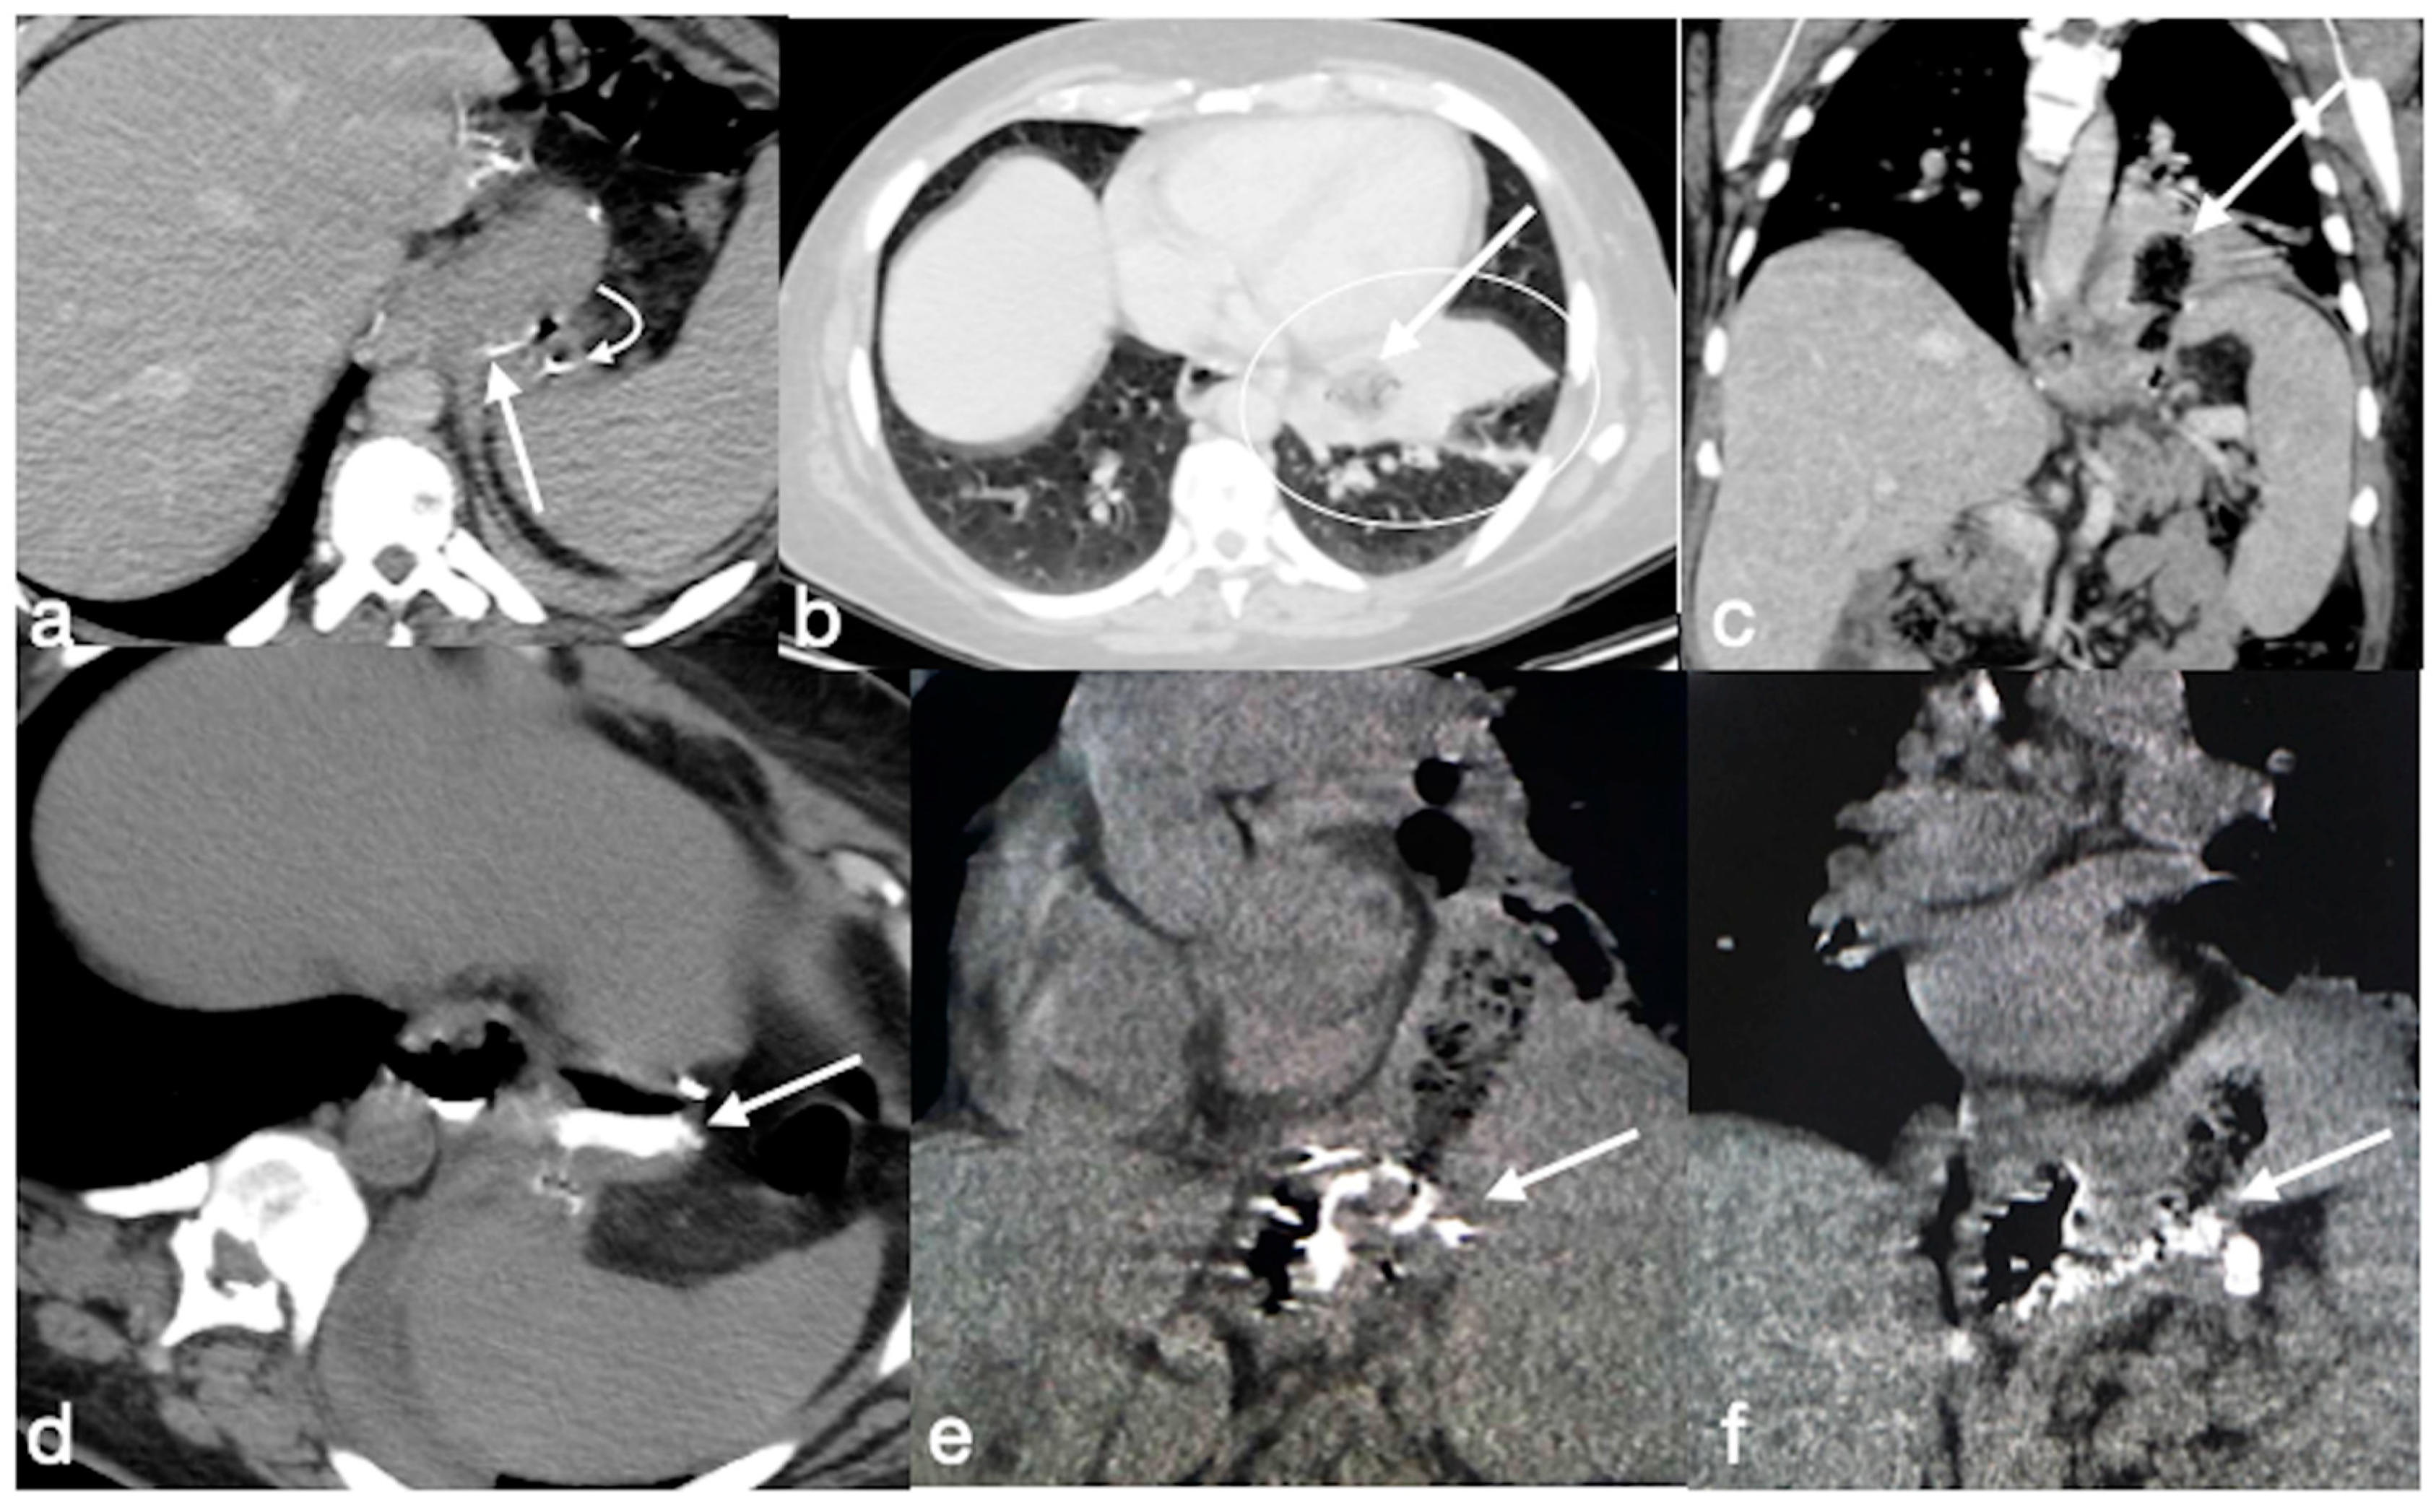

Figure 20. Patient 2. Suture leak with spleen abscess after sleeve gastrectomy. A 48-year-old patient underwent sleeve gastrectomy and complained in the following days of abdominal pain, fever, and dyspnea. At the first CT examination is seen the leak (a, axial view, straight arrow), free peritoneal fluid (a, curved arrow) and inhomogeneous enhancement of the spleen (a, circle). In more cranial scans, a splenic abscess is seen (b, circle) associated with the reactive pleural effusion (b, curved arrow), and the coronal view (c) further clarifies the finding (c, circle, splenic abscess). It was decided that the patient should be managed with percutaneous drainage of the splenic abscess. The patient came back after the drainage positioning, with chest pain and dyspnea (df) and at CT the left anterior pneumothorax (d, axial view, curved arrow) was detected due to the drainage positioning, which is actually in the splenic abscess (e, axial view, circle). However, in its course it crosses the left diaphragm (f, coronal view, circle).